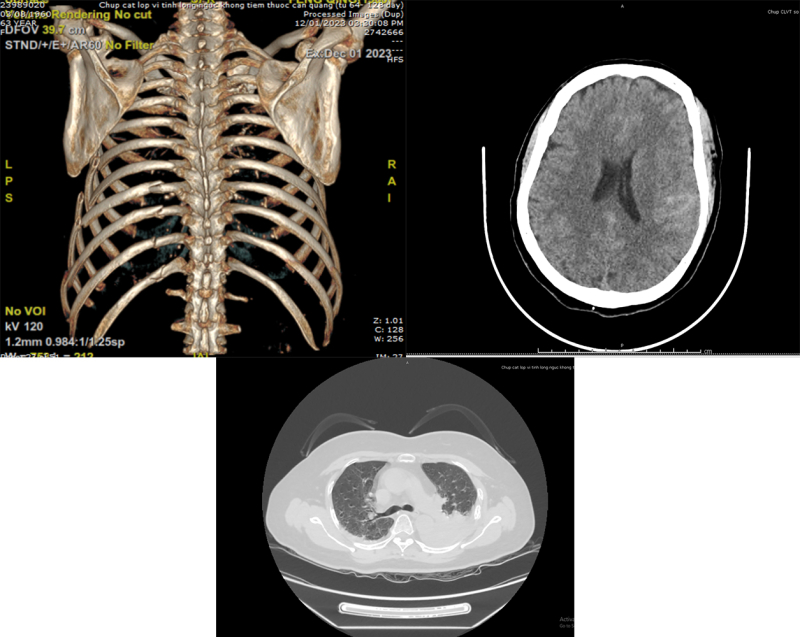

Hình ảnh chấn thương lồng ngực, sọ não, thận của bệnh nhân trên phim chụp CTscanner

Nữ bệnh nhân người Trung Quốc F.Q 63 tuổi vào viện cấp cứu sau tai nạn giao thông trong tình trạng đau ngực trái nhiều, đau đầu, sưng nề vùng mặt, cẳng tay… Qua thăm khám lâm sàng, thực hiện các xét nghiệm, chẩn đoán hình ảnh chuyên sâu như siêu âm, xquang, chụp CT Scanner..., các bác sĩ đã hội chẩn và thống nhất chẩn đoán đa chấn thương gồm: chấn thương sọ não (xuất hiện dưới nhện bán cầu não trái), chấn thương lồng ngực (gãy phức tạp nhiều xương sườn, dập phổi, tràn dịch màng phổi trái), vỡ thận, gãy cung tiếp gò má trái. Đánh giá tình trạng bệnh nhân nguy kịch, các bác sĩ đã khẩn trương can thiệp mở màng phổi, hút dẫn lưu khoang màng phổi bằng máy hút áp lực âm liên tục.